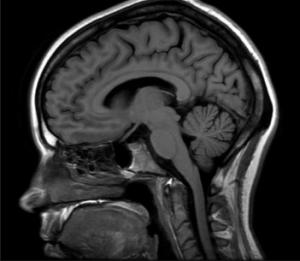

Recinto de Ciencias Médicas estrena la instalación, que es la más avanzada en el Caribe y Latinoamérica Con una inversión de $4 millones, la Clínica de la Escuela de Medicina del recinto de Ciencias Médicas (RCM) estrenará su nuevo Centro de Imágenes, que cuenta con equipos de resonancia magnética (MRI) y tomografía computarizada (CT Scan), únicos…